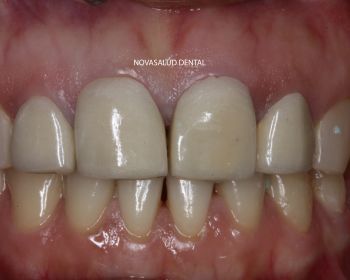

Tratamiento: coronas ceramo-metal unitarias en frente anterior.

Paciente acude a consulta con 4 coronas en sector anterior recién colocadas en otra clínica dental. La paciente no esta nada contenta con el resultado estético. Nos pide que le cambiemos las coronas. Decidimos retirar las 4 piezas ferulizadas y realizar 4 coronas unitarias, es decir, separadas individualmente para ganar en estética. El paciente mejora la estética dental con el tratamiento.